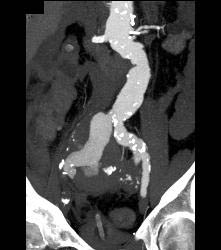

Iliac Artery Aneurysm With Leak